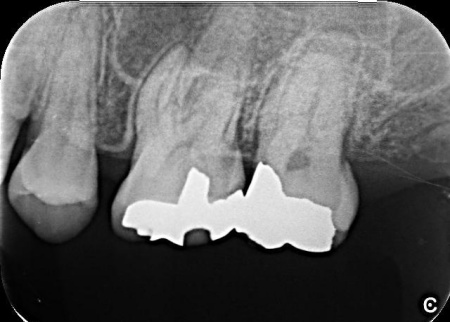

まずは、左上奥歯に装着されていた既存の詰め物を取り外し、根管内部を確認します。

続いて、マイクロスコープを使用しながら専用の器具を用いて根管内の感染した組織を丁寧に除去し、消毒薬で根管内を十分に洗浄します。

感染が広範囲に及んでいたため、複数回にわたり洗浄と消毒を実施しました。

根管内部の洗浄と消毒が完了したら、根管の内部を密封する処置を行います。

今回は、歯とのなじみがよく、歯根の先や複雑な形の部分にも適応しやすいMTAという材料を使用しました。

最後にレントゲン撮影を行い、根管がしっかりと封鎖されていることを確認して、治療を終了しています。